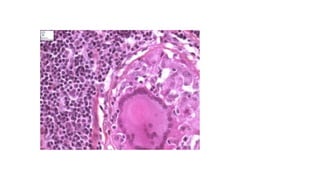

Granulomatous inflammation is a distinctive pattern

of chronic inflammation that is encountered in a

limited number of infectious and some

noninfectious conditions. Immune reactions are

usually involved in the development of

granulomas.

A granuloma is a cellular attempt to control an

offending agent that is difficult to eradicate.

.

• In this attempt there is often strong

activation of T lymphocytes leading to

macrophage activation, which can cause

injury to normal tissues

A granuloma is a focus of chronic

inflammation consisting of

a microscopic aggregation of

macrophages

that are transformed into epithelium-

like cells, surrounded by a collar of

mononuclear leukocytes, principally

lymphocytes and occasionally

plasma cells.

Older granulomas develop an enclosing rim of

fibroblasts and connective tissue.

Frequently, epithelioid cells fuse to form giant cells

in the periphery or sometimes in the center of

These giant cells may attain diameters of 40 to 50

μm.

peripherally (Langhans-type giant cell) or

haphazardly (foreign body–type giant cell).